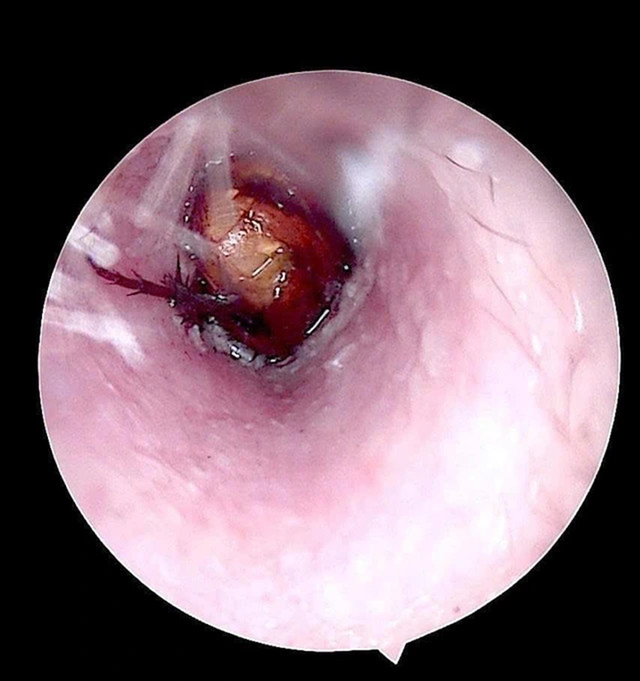

Tại viện qua kiểm tra, bác sĩ ghi nhận ống tai ngoài bên phải của bệnh nhân có hiện tượng xung huyết, có dị vật sống. Các bác sĩ đã tiến hành nội soi, gắp dị vật là một con côn trùng có kích thước khoảng 1,5cm.

Kiểm tra sau lấy dị vật, phát hiện màng nhĩ bệnh nhân nề đỏ do phản ứng viêm và kích thích trong quá trình tự lấy dị vật.

Hình ảnh côn trùng sống trong ống tai của bệnh nhân.